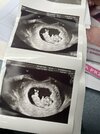

Cześć, byłam wczoraj na prenatalnych, z tego co lekarz tłumaczył wszystko jest ok i na miejscu. Ze względu na wysoką wolną beta HCG ryzyko trisomii 21 skorygowane mam 1:579, więc nie najlepiej. Pozostałe bardzo małe ryzyka. Niestety, nie był w stanie mi powiedzieć, dlaczego ta beta jest tak wysoka. USG minimalnie mnie uspokoiło, zabrałam męża żeby zobaczył swoje pierworodne i był zafascynowany

Mój ginekolog prowadzący chce mnie jeszcze raz przebadać, ale u siebie w szpitalu jak będzie miał dyżur, tam podobno ma najlepszy sprzęt, więc więcej dowiemy się w niedzielę.